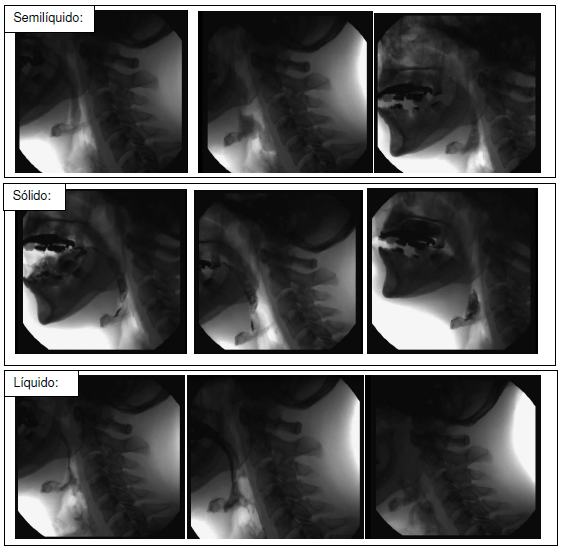

Alberto Roberto tem 62 anos, foi internado devido a acidente vascular cerebral e evoluiu com dificuldade de deglutição e comunicação, tendo sido submetido a nutrição enteral através de sonda nasogástrica. A equipe da enfermaria solicitou avaliação fonoaudiológica quanto à possibilidade de alimentação por via oral e a fonoaudióloga responsável optou por solicitar videofluoroscopia da deglutição para esclarecimento diagnóstico, cujos achados estão expressos abaixo:

a) Considerando as imagens da avaliação videofluoroscópica de Alberto Roberto, cite 2 (dois) achados clínicos e suas respectivas justificativas fisiopatológicas.

b) Cite 2 (duas) es…